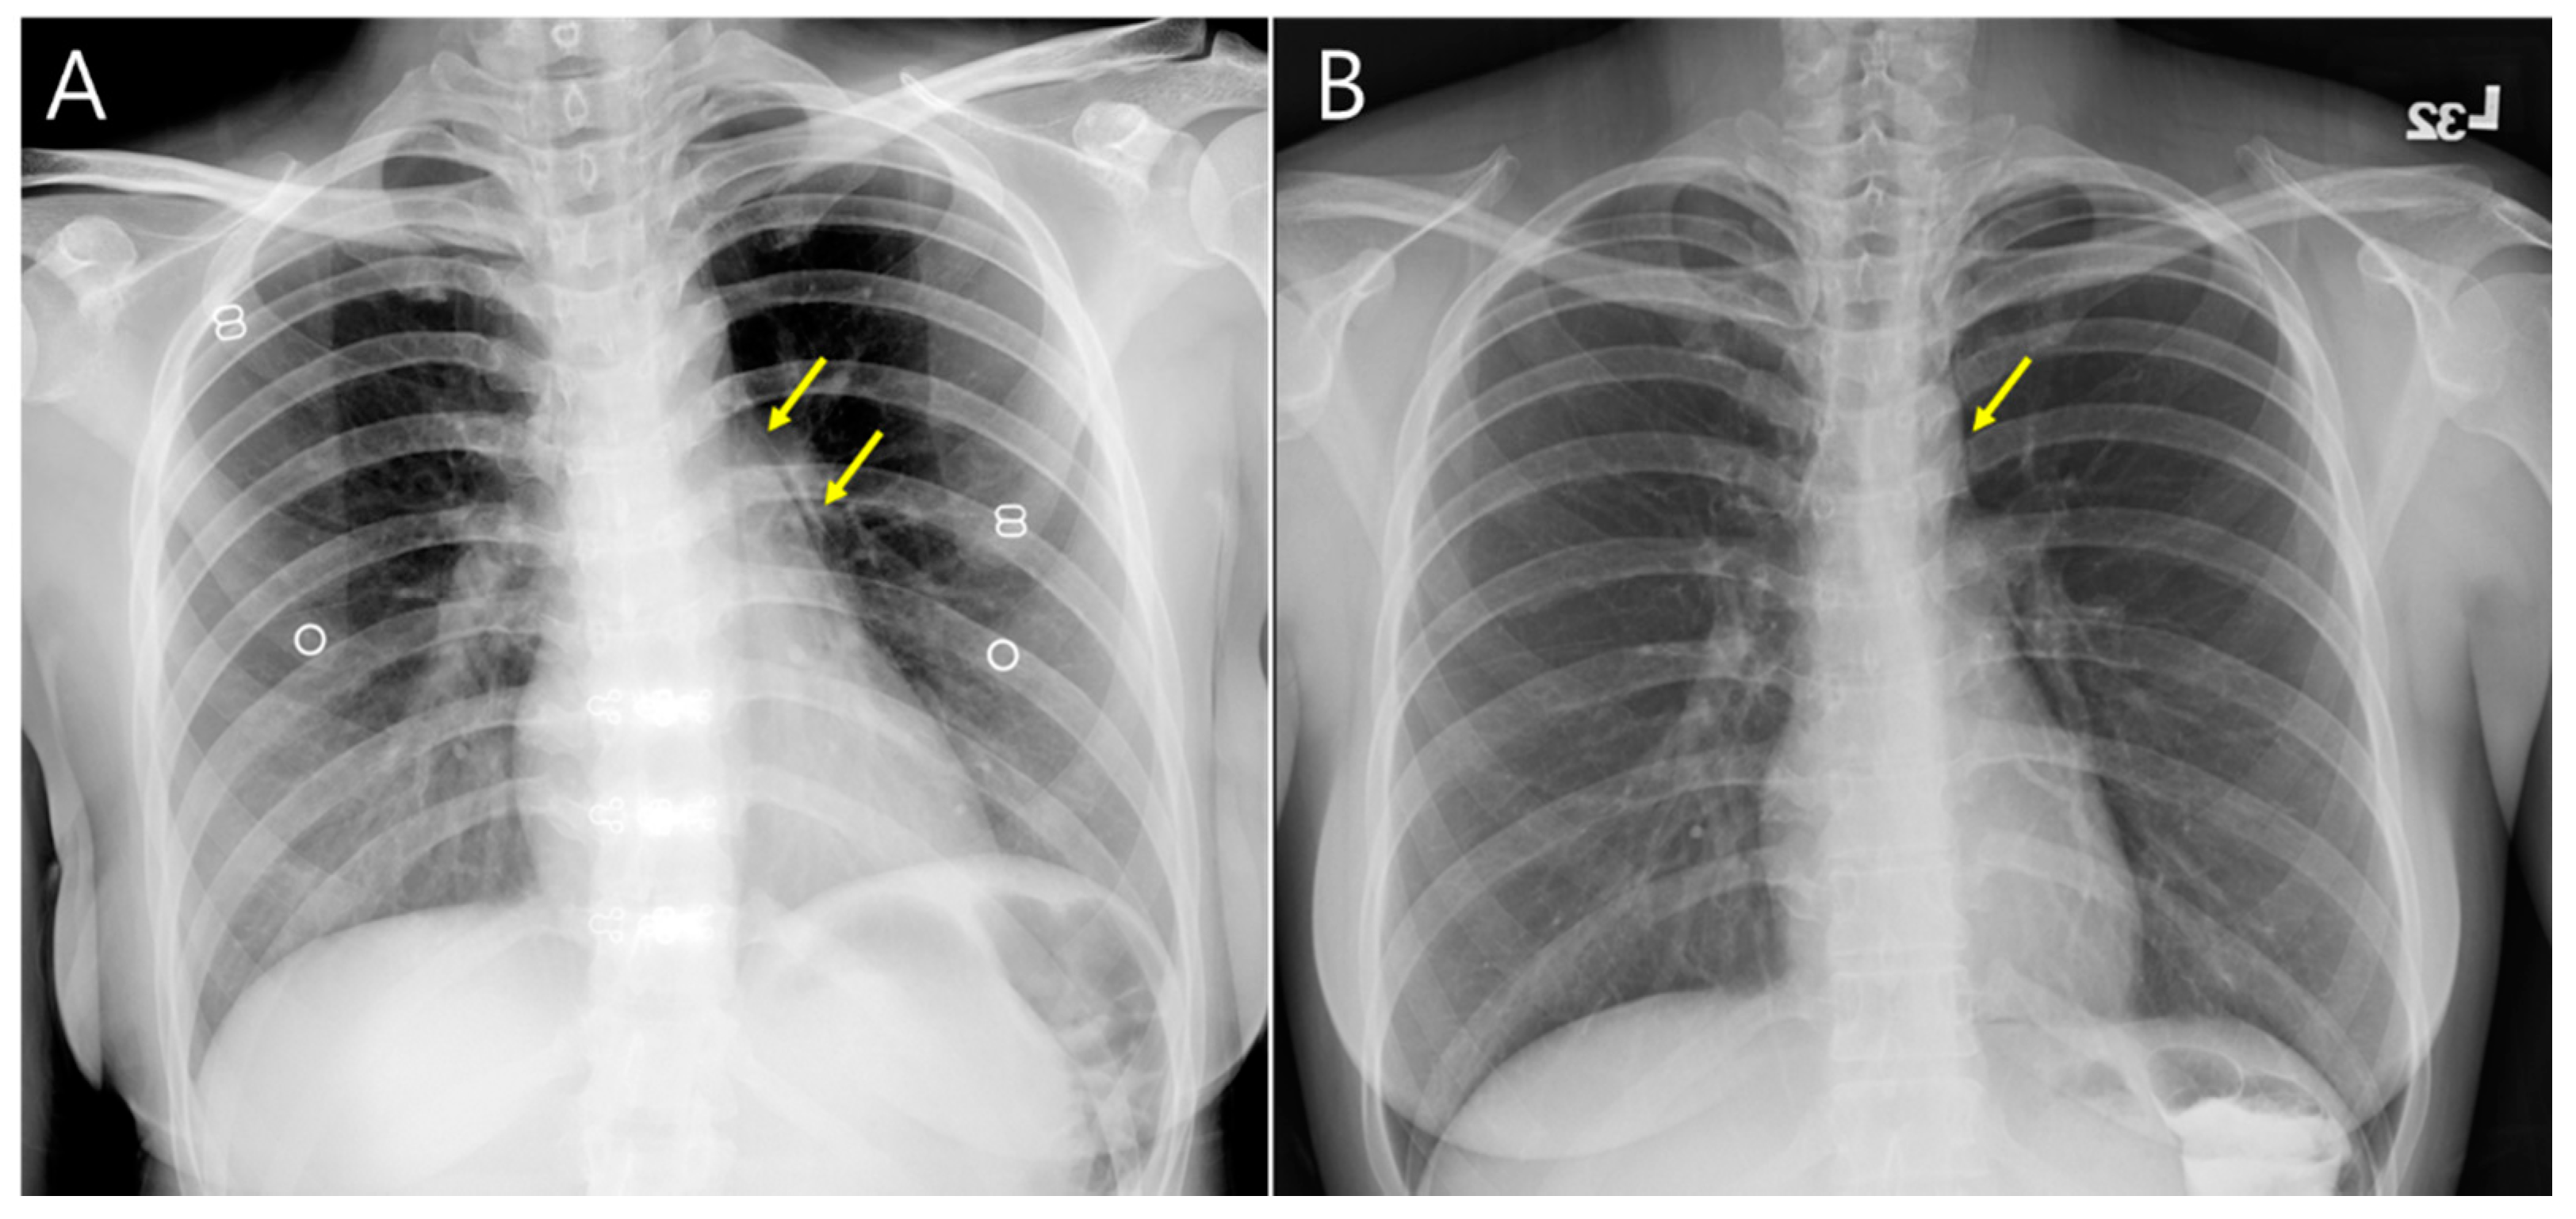

2. Case Presentation